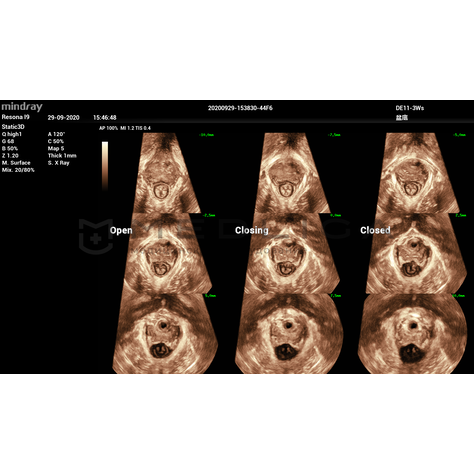

Smart Pelvic - новое решение, позволяющее значительно упростить диагностическую процедуру и свести к минимуму время исследования функций мышц тазового дна. Благодаря чрезвычайно простому пользовательскому интерфейсу, программа генерирует стандартную систему координат и автоматически просчитывает все связанные измерения в течение нескольких секунд.